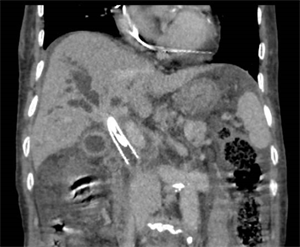

患者是一名79岁的女性,因皮肤、巩膜黄染,尿色加深3天就诊于我院。入院肝功结果提示胆红素升高,总胆红素高达422umol/L。肝脏增强MRI提示:肝总管/胆囊管汇合处肿物,考虑恶性,并继发肝内胆管扩张。初步诊断为肝总管肿物、梗阻性黄疸。经腹部肿瘤外科会诊认为该患高龄,且肿物位于肝门部,外科手术风险大,出血几率高,家属不同意行外科治疗。孙志强团队会诊后判断,该患梗阻部位处于肝总管、胆囊管交汇处,属高位胆管梗阻,不宜行内镜下逆行胆管引流术(ERCP),可行经皮肝穿刺胆管引流术(PTCD),再根据胆管造影情况来判断能否行胆道支架置入术。拟行DSA引导下胆道活检联合胆道支架植入术,为后续治疗创造机会,患者家属表示同意,要求行该治疗方案。在明确患者没有手术禁忌症后,团队于CT导引下行PTCD,后于DSA导引下行胆管造影。因胆管梗阻严重,造影后无法通过,即便利用导丝导引也十分困难。经过反复尝试和更换不同硬度导丝后,终于导丝越过梗阻部位,导丝导引导管成功完成胆道造影,明确了梗阻的部位和长度,最终顺利完成了本次胆道支架置入手术。

术后第2天,患者皮肤、巩膜黄染缓解,尿色变浅,胆汁引流量较前减少,复查肝功能,总胆红素降至264 umol/L,取得了立竿见影的效果。1周后患者胆汁引流量明显减少,总胆红素降至98 umol/L。再次分析病情,拟复查胆道造影明确目前梗阻缓解情况,若胆道通畅可考虑拔除胆道引流管。但患者目前无病理学诊断支持,即便影像学诊断为胆管恶性肿瘤,但病理诊断才是胆管癌诊断的金标准。再次研判病情后,决定术中利用胆道活检毛刷进行刷检,明确肿物性质。术中行胆道造影可见造影剂顺利通过狭窄部位并进入十二指肠,证实胆管通畅,而后行胆道刷检术,成功刷取胆道病变组织一块,送病理活检结果回报示:考虑恶性,倾向腺癌。最终明确诊断为:胆管癌,为接下来的抗肿瘤治疗提供了可靠的证据。